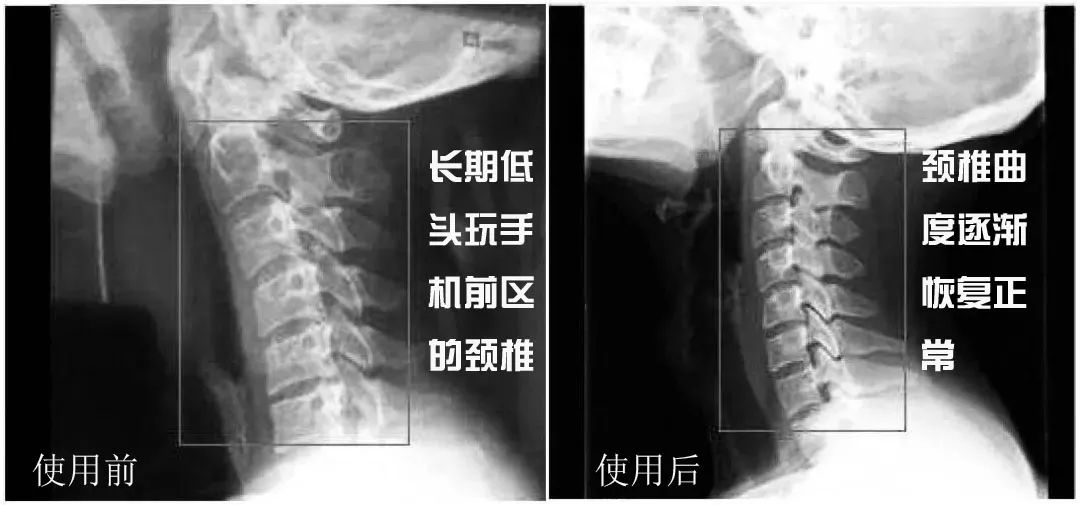

办公室有个小哥喜欢低头玩手机

颈椎前倾很严重,看起来像“驼背”一样

听说了这款九木枕后,第一时间就买了1个

到现在睡了一段时间后,整个人都直挺了不少

他还不放心,去yi院拍了CT

yi生惊讶的告诉他:

你的颈椎曲度已经恢复了80%!